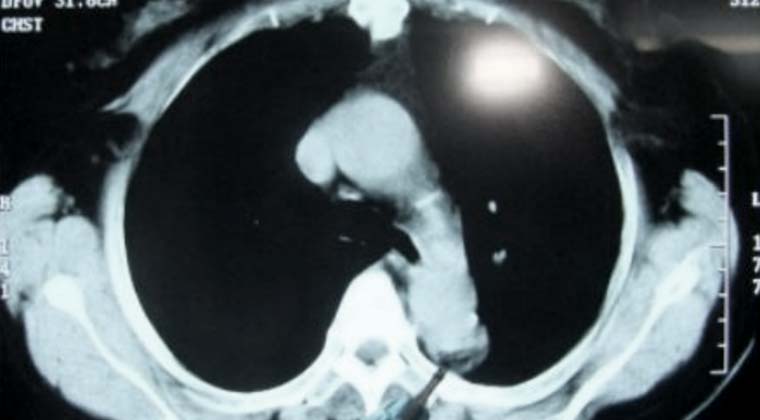

② Случай 2:

Очаговое образование в верхней доле левого легкого, прилежащее к аорте, вероятно является метастатической опухолью.

(Опухоль, на которую указывает кончик зонда)

(Область некроза опухолевой ткани, на которую указывает кончик зонда)